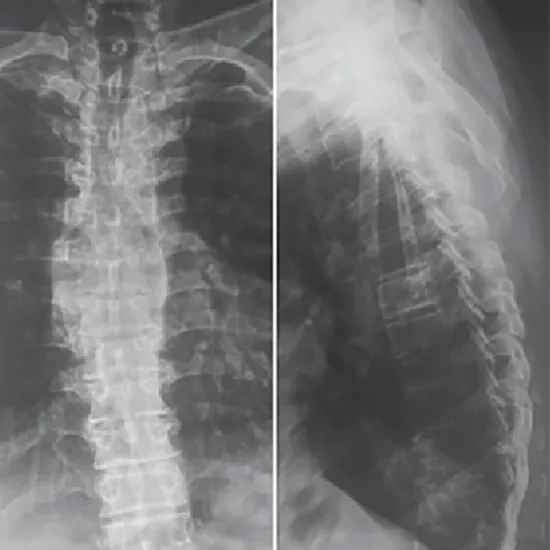

X-ray Dorso Lumbar Spine AP View

The X-ray Dorso Lumbar Spine AP View is a test that shows the bones of the lower back (the thoracic and lumbar spinal columns) and the discs between them and the skin and muscles around them.